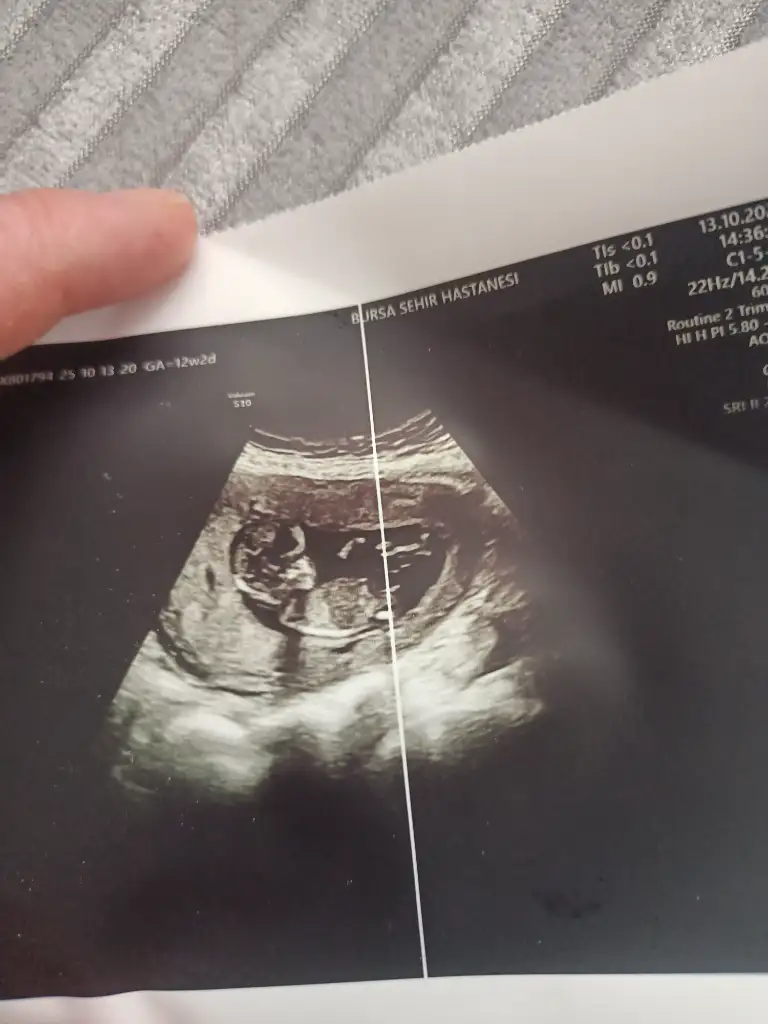

13+6 rica etsem bana da bakar mısınız

Eklentiler

• IMG20250620181644.webp

17,4 KB · Görüntüleme: 41

• IMG20250620181647.webp

22,6 KB · Görüntüleme: 32